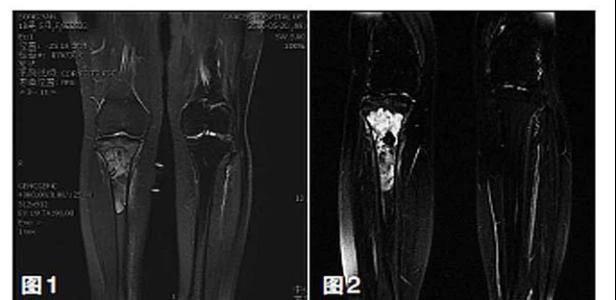

新輔助化療的目的是盡早殺滅遠(yuǎn)處微小轉(zhuǎn)移灶,縮小腫瘤及周圍炎性水腫反應(yīng)區(qū),以利于后續(xù)的保肢手術(shù);觀察腫瘤對(duì)化療的敏感性,為進(jìn)一步指定個(gè)體化的術(shù)后化療方案奠定基礎(chǔ)。骨肉瘤新輔助化療下的保肢治療如下圖所示: